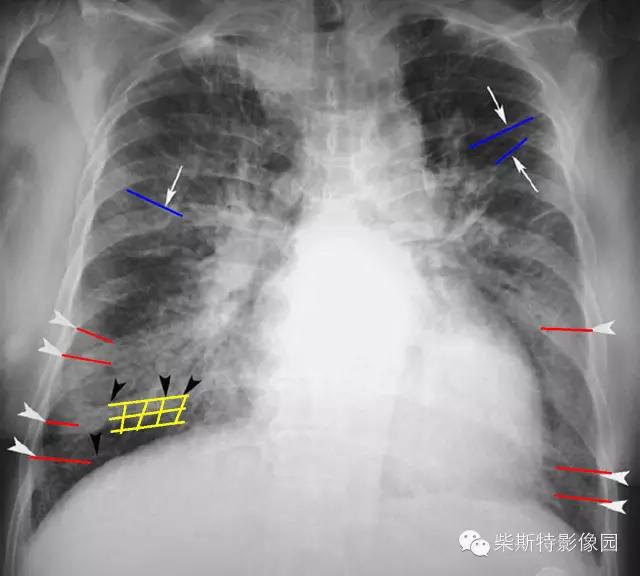

经典图像第一例:

小编标注:蓝色线是克氏A线,红色线是克氏B线,黄色网格状线是克氏C线。

1.A线:表现为直的或近乎直的指向肺门的不分支的致密细线影,呈水平走行,长度约2~4cm,但很少超过4cm,宽度为0.5~1mm。多见于上肺野。

2.B线:为克氏线征中最常见者,表现为较短的不分又的梯状致密横线影,长不超过2cm,宽不超过1mm。常位于两下肺野的外带(肋隔角)平行的次出现,亦可见于中肺野,但从不出现于上肺野。其外端常抵达胸膜缘并与之垂直,以右侧为多见.

3.C线:少见,表现为很细很短的线状影,可向任何方向走行,相互交织呈蛛网状影。其可见于肺的任何部分,好发于下肺。